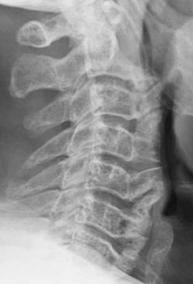

DISH is characterized by flowing hyperostosis of the anterior longitudinal ligament, involving at least four continuous vertebral levels. Enthesopathy at the site of tendinous and ligamentous attachments, especially about the pelvis, is also characteristic. DISH is most common in the thoracic spine, but also occurs in the cervical and lumbar spine. Intervertebral disc heights tend to be maintained due to the “scaffolding” effect provided by the ossification anteriorly. Clinically, DISH tends to be either asymptomatic or present as spinal stiffness. However, there are several associated conditions and risk factors that should be considered and assessed in your patients with DISH, as some can have serious clinical consequences. Some of the associated conditions and risk factors include: 1) Ossification of the posterior longitudinal ligament; 2) chalk stick fracture; and 3) dysphagia.

3) Dysphagia

Bulky hyperostosis the anterior longitudinal ligament in the cervical spine can result in posterior compression of the esophagus. Resection of the bulky hyperostosis in the region may be needed to relieve the mechanical symptoms.